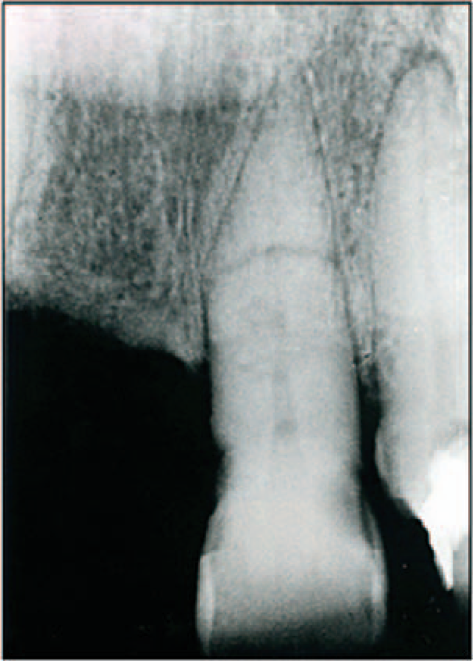

Hypercementosis

Excess cementum formation